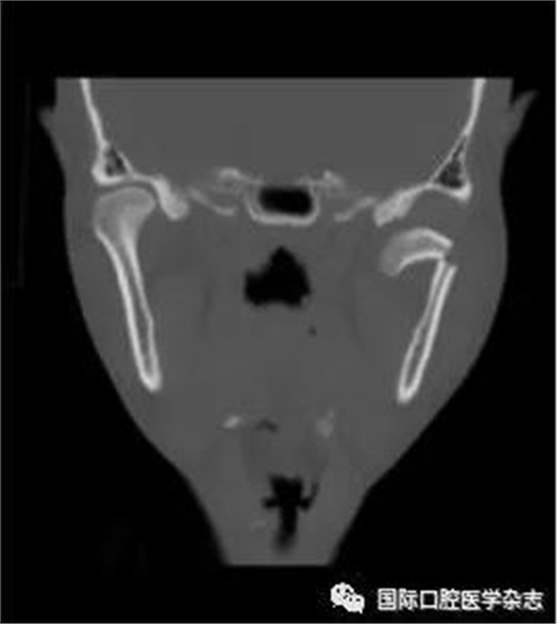

(4)關節(jié)強直(圖3):指因器質性病變導致長期開口困難或完全不能開口??煞譃殛P節(jié)內強直和關節(jié)外強直。關節(jié)內強直是由于一側或兩側關節(jié)內發(fā)生病變,造成關節(jié)內的纖維性或骨性粘連,也有人稱為真性關節(jié)強直。關節(jié)外強直是病變位于關節(jié)外上下頜間皮膚、黏膜或深層肌肉組織,形成頜間瘢痕攣縮(圖4),也有人稱為假性關節(jié)強直[7]。5)顳下頜關節(jié)感染:常由下頜關節(jié)附近化膿性病灶所致。多見于兒童中耳炎、腮腺炎等。此外還可由全身性傳染性疾病如麻疹、猩紅熱等引起。6)顳下頜關節(jié)外傷(圖5):外傷是引起開口受限的常見因素之一,最常見于下頜骨髁突骨折引起下頜運動受限[8]。

圖 3 關節(jié)內強直